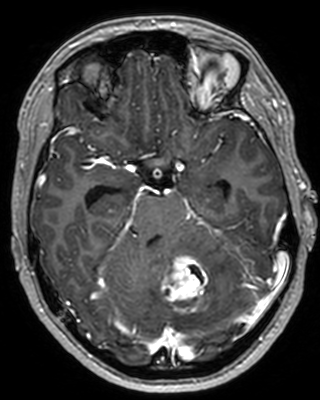

Refer to captionRefer to caption𝐱PCsubscript𝐱PC\mathbf{x}_{\mathrm{PC}}bold_x start_POSTSUBSCRIPT roman_PC end_POSTSUBSCRIPTRefer to captionRefer to caption𝐱LDsubscript𝐱LD\mathbf{x}_{\mathrm{LD}}bold_x start_POSTSUBSCRIPT roman_LD end_POSTSUBSCRIPTRefer to captionRefer to caption𝐱SDsubscript𝐱SD\mathbf{x}_{\mathrm{SD}}bold_x start_POSTSUBSCRIPT roman_SD end_POSTSUBSCRIPTRefer to captionRefer to captionAm-3D [14]Refer to captionRefer to captionPa-2.5D [8]Refer to captionRefer to caption𝐱~SDsubscript~𝐱SD\tilde{\mathbf{x}}_{\mathrm{SD}}over~ start_ARG bold_x end_ARG start_POSTSUBSCRIPT roman_SD end_POSTSUBSCRIPT (ours)ptPhilips Achieva 3TGadobutrol dLD=0.10subscript𝑑LD0.10d_{\mathrm{LD}}=0.10italic_d start_POSTSUBSCRIPT roman_LD end_POSTSUBSCRIPT = 0.10ptPhilips Ingenia 1.5TGadoterate dLD=0.33subscript𝑑LD0.33d_{\mathrm{LD}}=0.33italic_d start_POSTSUBSCRIPT roman_LD end_POSTSUBSCRIPT = 0.33Refer to captionRefer to caption𝐱PCsubscript𝐱PC\mathbf{x}_{\mathrm{PC}}bold_x start_POSTSUBSCRIPT roman_PC end_POSTSUBSCRIPTRefer to captionRefer to caption𝐱LDsubscript𝐱LD\mathbf{x}_{\mathrm{LD}}bold_x start_POSTSUBSCRIPT roman_LD end_POSTSUBSCRIPTRefer to captionRefer to caption𝐱SDsubscript𝐱SD\mathbf{x}_{\mathrm{SD}}bold_x start_POSTSUBSCRIPT roman_SD end_POSTSUBSCRIPTRefer to captionRefer to captionAm-3D [14]Refer to captionRefer to captionPa-2.5D [8]Refer to captionRefer to caption𝐱~SDsubscript~𝐱SD\tilde{\mathbf{x}}_{\mathrm{SD}}over~ start_ARG bold_x end_ARG start_POSTSUBSCRIPT roman_SD end_POSTSUBSCRIPT (ours)ptPhilips Achieva 3TGadobutrol dLD=0.10subscript𝑑LD0.10d_{\mathrm{LD}}=0.10italic_d start_POSTSUBSCRIPT roman_LD end_POSTSUBSCRIPT = 0.10ptPhilips Ingenia 1.5TGadoterate dLD=0.33subscript𝑑LD0.33d_{\mathrm{LD}}=0.33italic_d start_POSTSUBSCRIPT roman_LD end_POSTSUBSCRIPT = 0.33Refer to captionRefer to caption𝐱PCsubscript𝐱PC\mathbf{x}_{\mathrm{PC}}bold_x start_POSTSUBSCRIPT roman_PC end_POSTSUBSCRIPTRefer to captionRefer to caption𝐱LDsubscript𝐱LD\mathbf{x}_{\mathrm{LD}}bold_x start_POSTSUBSCRIPT roman_LD end_POSTSUBSCRIPTRefer to captionRefer to caption𝐱SDsubscript𝐱SD\mathbf{x}_{\mathrm{SD}}bold_x start_POSTSUBSCRIPT roman_SD end_POSTSUBSCRIPTRefer to captionRefer to captionAm-3D [14]Refer to captionRefer to captionPa-2.5D [8]Refer to captionRefer to caption𝐱~SDsubscript~𝐱SD\tilde{\mathbf{x}}_{\mathrm{SD}}over~ start_ARG bold_x end_ARG start_POSTSUBSCRIPT roman_SD end_POSTSUBSCRIPT (ours)ptPhilips Achieva 3TGadobutrol dLD=0.10subscript𝑑LD0.10d_{\mathrm{LD}}=0.10italic_d start_POSTSUBSCRIPT roman_LD end_POSTSUBSCRIPT = 0.10ptPhilips Ingenia 1.5TGadoterate dLD=0.33subscript𝑑LD0.33d_{\mathrm{LD}}=0.33italic_d start_POSTSUBSCRIPT roman_LD end_POSTSUBSCRIPT = 0.33Refer to captionRefer to caption𝐱PCsubscript𝐱PC\mathbf{x}_{\mathrm{PC}}bold_x start_POSTSUBSCRIPT roman_PC end_POSTSUBSCRIPTRefer to captionRefer to caption𝐱LDsubscript𝐱LD\mathbf{x}_{\mathrm{LD}}bold_x start_POSTSUBSCRIPT roman_LD end_POSTSUBSCRIPTRefer to captionRefer to caption𝐱SDsubscript𝐱SD\mathbf{x}_{\mathrm{SD}}bold_x start_POSTSUBSCRIPT roman_SD end_POSTSUBSCRIPTRefer to captionRefer to captionAm-3D [14]Refer to captionRefer to captionPa-2.5D [8]Refer to captionRefer to caption𝐱~SDsubscript~𝐱SD\tilde{\mathbf{x}}_{\mathrm{SD}}over~ start_ARG bold_x end_ARG start_POSTSUBSCRIPT roman_SD end_POSTSUBSCRIPT (ours)ptPhilips Achieva 3TGadobutrol dLD=0.10subscript𝑑LD0.10d_{\mathrm{LD}}=0.10italic_d start_POSTSUBSCRIPT roman_LD end_POSTSUBSCRIPT = 0.10ptPhilips Ingenia 1.5TGadoterate dLD=0.33subscript𝑑LD0.33d_{\mathrm{LD}}=0.33italic_d start_POSTSUBSCRIPT roman_LD end_POSTSUBSCRIPT = 0.33Refer to captionRefer to caption𝐱PCsubscript𝐱PC\mathbf{x}_{\mathrm{PC}}bold_x start_POSTSUBSCRIPT roman_PC end_POSTSUBSCRIPTRefer to captionRefer to caption𝐱LDsubscript𝐱LD\mathbf{x}_{\mathrm{LD}}bold_x start_POSTSUBSCRIPT roman_LD end_POSTSUBSCRIPTRefer to captionRefer to caption𝐱SDsubscript𝐱SD\mathbf{x}_{\mathrm{SD}}bold_x start_POSTSUBSCRIPT roman_SD end_POSTSUBSCRIPTRefer to captionRefer to captionAm-3D [14]Refer to captionRefer to captionPa-2.5D [8]Refer to captionRefer to caption𝐱~SDsubscript~𝐱SD\tilde{\mathbf{x}}_{\mathrm{SD}}over~ start_ARG bold_x end_ARG start_POSTSUBSCRIPT roman_SD end_POSTSUBSCRIPT (ours)ptPhilips Achieva 3TGadobutrol dLD=0.10subscript𝑑LD0.10d_{\mathrm{LD}}=0.10italic_d start_POSTSUBSCRIPT roman_LD end_POSTSUBSCRIPT = 0.10ptPhilips Ingenia 1.5TGadoterate dLD=0.33subscript𝑑LD0.33d_{\mathrm{LD}}=0.33italic_d start_POSTSUBSCRIPT roman_LD end_POSTSUBSCRIPT = 0.33Refer to captionRefer to caption𝐱PCsubscript𝐱PC\mathbf{x}_{\mathrm{PC}}bold_x start_POSTSUBSCRIPT roman_PC end_POSTSUBSCRIPTRefer to captionRefer to caption𝐱LDsubscript𝐱LD\mathbf{x}_{\mathrm{LD}}bold_x start_POSTSUBSCRIPT roman_LD end_POSTSUBSCRIPTRefer to captionRefer to caption𝐱SDsubscript𝐱SD\mathbf{x}_{\mathrm{SD}}bold_x start_POSTSUBSCRIPT roman_SD end_POSTSUBSCRIPTRefer to captionRefer to captionAm-3D [14]Refer to captionRefer to captionPa-2.5D [8]Refer to captionRefer to caption𝐱~SDsubscript~𝐱SD\tilde{\mathbf{x}}_{\mathrm{SD}}over~ start_ARG bold_x end_ARG start_POSTSUBSCRIPT roman_SD end_POSTSUBSCRIPT (ours)ptPhilips Achieva 3TGadobutrol dLD=0.10subscript𝑑LD0.10d_{\mathrm{LD}}=0.10italic_d start_POSTSUBSCRIPT roman_LD end_POSTSUBSCRIPT = 0.10ptPhilips Ingenia 1.5TGadoterate dLD=0.33subscript𝑑LD0.33d_{\mathrm{LD}}=0.33italic_d start_POSTSUBSCRIPT roman_LD end_POSTSUBSCRIPT = 0.33Refer to captionRefer to caption𝐱PCsubscript𝐱PC\mathbf{x}_{\mathrm{PC}}bold_x start_POSTSUBSCRIPT roman_PC end_POSTSUBSCRIPTRefer to captionRefer to caption𝐱LDsubscript𝐱LD\mathbf{x}_{\mathrm{LD}}bold_x start_POSTSUBSCRIPT roman_LD end_POSTSUBSCRIPTRefer to captionRefer to caption𝐱SDsubscript𝐱SD\mathbf{x}_{\mathrm{SD}}bold_x start_POSTSUBSCRIPT roman_SD end_POSTSUBSCRIPTRefer to captionRefer to captionAm-3D [14]Refer to captionRefer to captionPa-2.5D [8]Refer to captionRefer to caption𝐱~SDsubscript~𝐱SD\tilde{\mathbf{x}}_{\mathrm{SD}}over~ start_ARG bold_x end_ARG start_POSTSUBSCRIPT roman_SD end_POSTSUBSCRIPT (ours)ptPhilips Achieva 3TGadobutrol dLD=0.10subscript𝑑LD0.10d_{\mathrm{LD}}=0.10italic_d start_POSTSUBSCRIPT roman_LD end_POSTSUBSCRIPT = 0.10ptPhilips Ingenia 1.5TGadoterate dLD=0.33subscript𝑑LD0.33d_{\mathrm{LD}}=0.33italic_d start_POSTSUBSCRIPT roman_LD end_POSTSUBSCRIPT = 0.33

Figure 6: Qualitative evaluation on the RLS dataset. The top row depicts a 33%percent3333\%33 % low-dose sample, where the yellow zoom highlights the lesion. The bottom row shows a case with a 10%percent1010\%10 % real low-dose image and the lesion is marked by the yellow circles.

A qualitative comparison of RLD test samples is shown in Figure 6. The required skull stripping and non-linear intensity normalization of Am-3D are readily apparent. Thus, a quantitative comparison to the target 𝐱SDsubscript𝐱SD\mathbf{x}_{\mathrm{SD}}bold_x start_POSTSUBSCRIPT roman_SD end_POSTSUBSCRIPT is not reasonable. Nevertheless, the CE signal strength in pathological regions (highlighted by the yellow circles) is well visible despite too smooth output images. The internal morphology and the border delineation also exhibit blurring. Pa-2.5D yields better image quality but the contrast strength in pathological regions is not well captured. In particular, the contrast signal overshoots for the 33%percent3333\%33 % low-dose scan in the first row and undershoots for the 10%percent1010\%10 % scan at the bottom, although the training dataset contains low-dose images at both dose levels. Our approach yields the highest image quality and predicts the contrast enhancement more accurately due to the focus on the enhancement signal and the conditional embeddings. As a result, our approach generates CE images preserving the image quality of the inputs by avoiding the synthesis of anatomical or noise patterns.